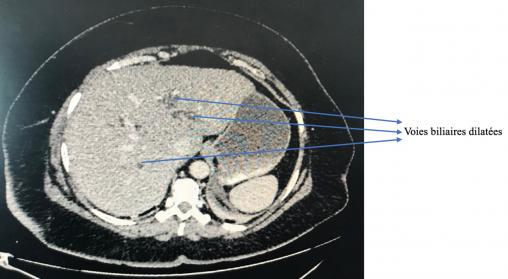

Dilatation des voies biliaires

PACS CHSD, La Revue du Praticien

Foie homogène avec voies biliaires trop bien visibles.